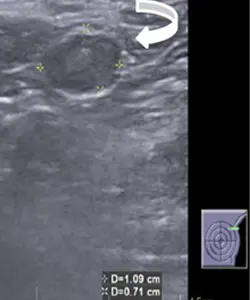

Left breast USG showing mass forming area consisting of multiple thickened dilated ducts extending into the subcutaneous region (straight white arrow). There is parenchymal edema surrounding this area of abnormality.

• In USG, breast tuberculosis can be seen as

• Nodular - Indistinct heterogenous hypoechoic mass

• Diffuse - form Ill defined hypoechoic masses.

• Skin thickening and duct ectasia are the other findings that are seen.